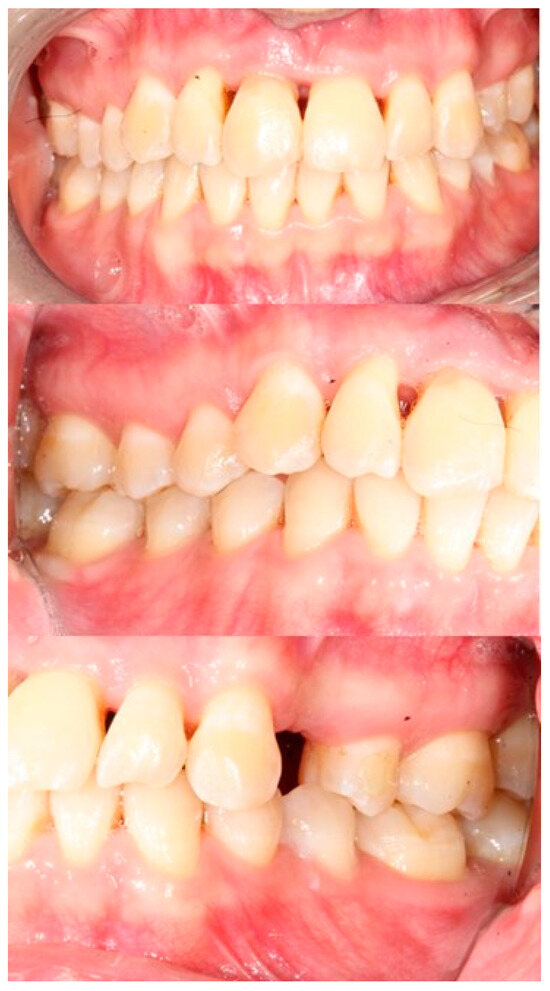

2. Case Report